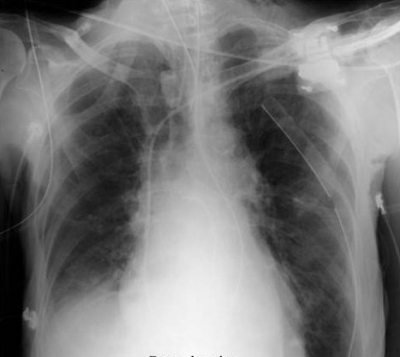

האבחנה של Flail chest היא קלינית ורנטגנית. בצילום חזה, ניתן לראות שברים בשני מקומות באותה הצלע במספר צלעות (תצלום 9.16). ב-CT חזה ניתן לראות תמונה דומה.